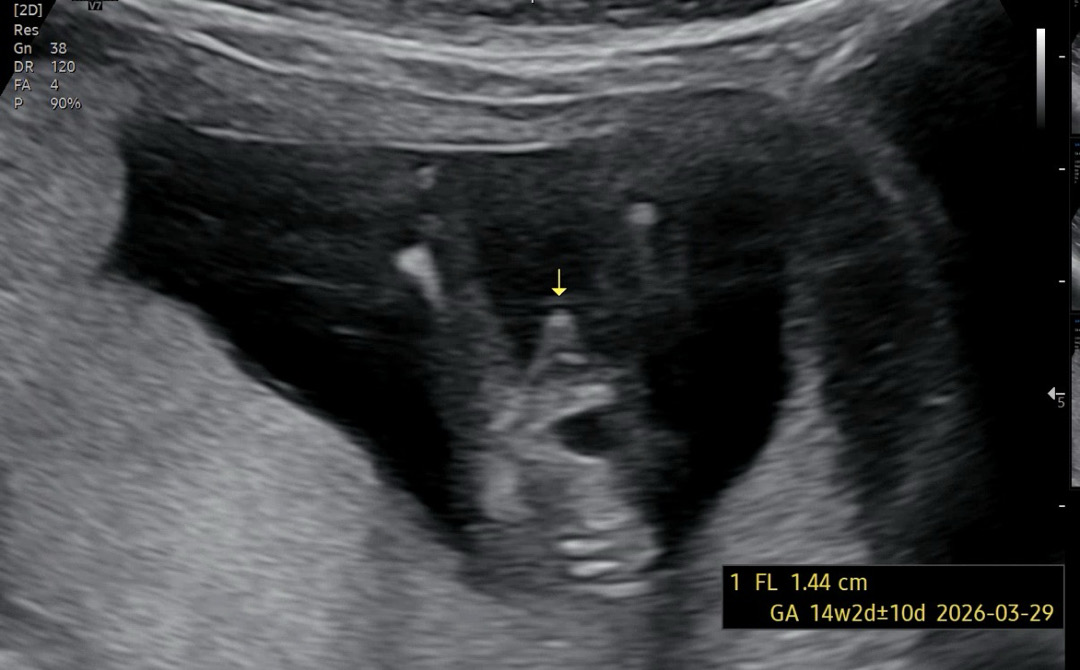

아들맘님들 초음파 원래 이런가용??

위에서볼때 🌶️가 다들 둥글게 보이시나요?? 검색해봤을땐 다 엉덩이사진밖에 안보여서요😅 엉덩이쪽으로 볼땐 뭔가 다들 뾰족한것같길래..? 지금 14주 5일인데 탯줄일순 없겠죠,,? ㅋㅋㅋㅋ

저도 14주 5일땬 둥근 삼각형 15주 1일차때 완전 고추처럼 보엿어여 ㅎㅎ

ㅎㅎ엉덩이쪽에서 봤을때 뭐가 보이면 거의 아들이래여 ~ 딸은 긴가민가하거나 없거나 !

서브병원으로 갔는데 엉덩이쪽은 안보여주시더라구용 ㅋㅋ 근데 위에서 봤을때도 존재감 또렷해서 확실한것같아용 ㅋㅋㅋ